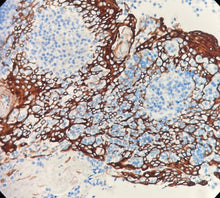

Cytokératine 5 & 6

Localisation : Cytoplasme

CK5/6 est une kératine basique de haut poids moléculaire. Elle est spécifiquement exprimée dans les cellules basales des épithéliums stratifiés, l’épithélium transitionnel, les cellules mésothéliales et l’épithélium squameux hyperplasique (CK6 est souvent co-exprimée avec CK16).

L’anticorps montre un taux de positivité proche de 100 % dans le mésothéliome malin (en contraste marqué avec l’adénocarcinome pulmonaire), tout en présentant une forte spécificité pour les carcinomes indifférenciés à grandes cellules et les carcinomes épidermoïdes. Son taux de positivité est inférieur à 10 % dans les cancers du sein, du côlon et de la prostate.

Contrôle positif : Tissu œsophagien